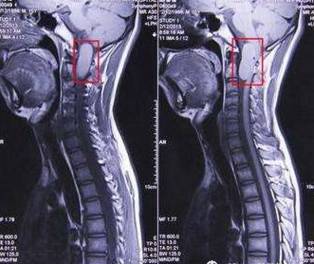

(一)椎管内疾患

1、极端或特异病变

(1)肿瘤:神经纤维瘤、神经鞘瘤、神经根囊肿、皮样囊肿、室管膜瘤、转移癌(肝、肾、前列腺、卵巢)、脊髓胶质细胞瘤、神经母细胞瘤等。

(2)血管瘤及变异:动静脉瘤、脊膜膨出。

(3)脊髓空洞症、多发性硬化。

2、常见疾患

(1)腰椎间盘突出症(中央型、侧旁型、外侧型、极外侧型、前方型)。

(2)胸腰椎管狭窄症(先天性、发育性、退变性、外伤性、医源性、混合性)

(3)腰椎滑移症(导致继发性椎管狭窄)。

(4)软组织损害(黄韧带肥厚、后纵韧带钙化、脂肪结缔组织变性挛缩等)。